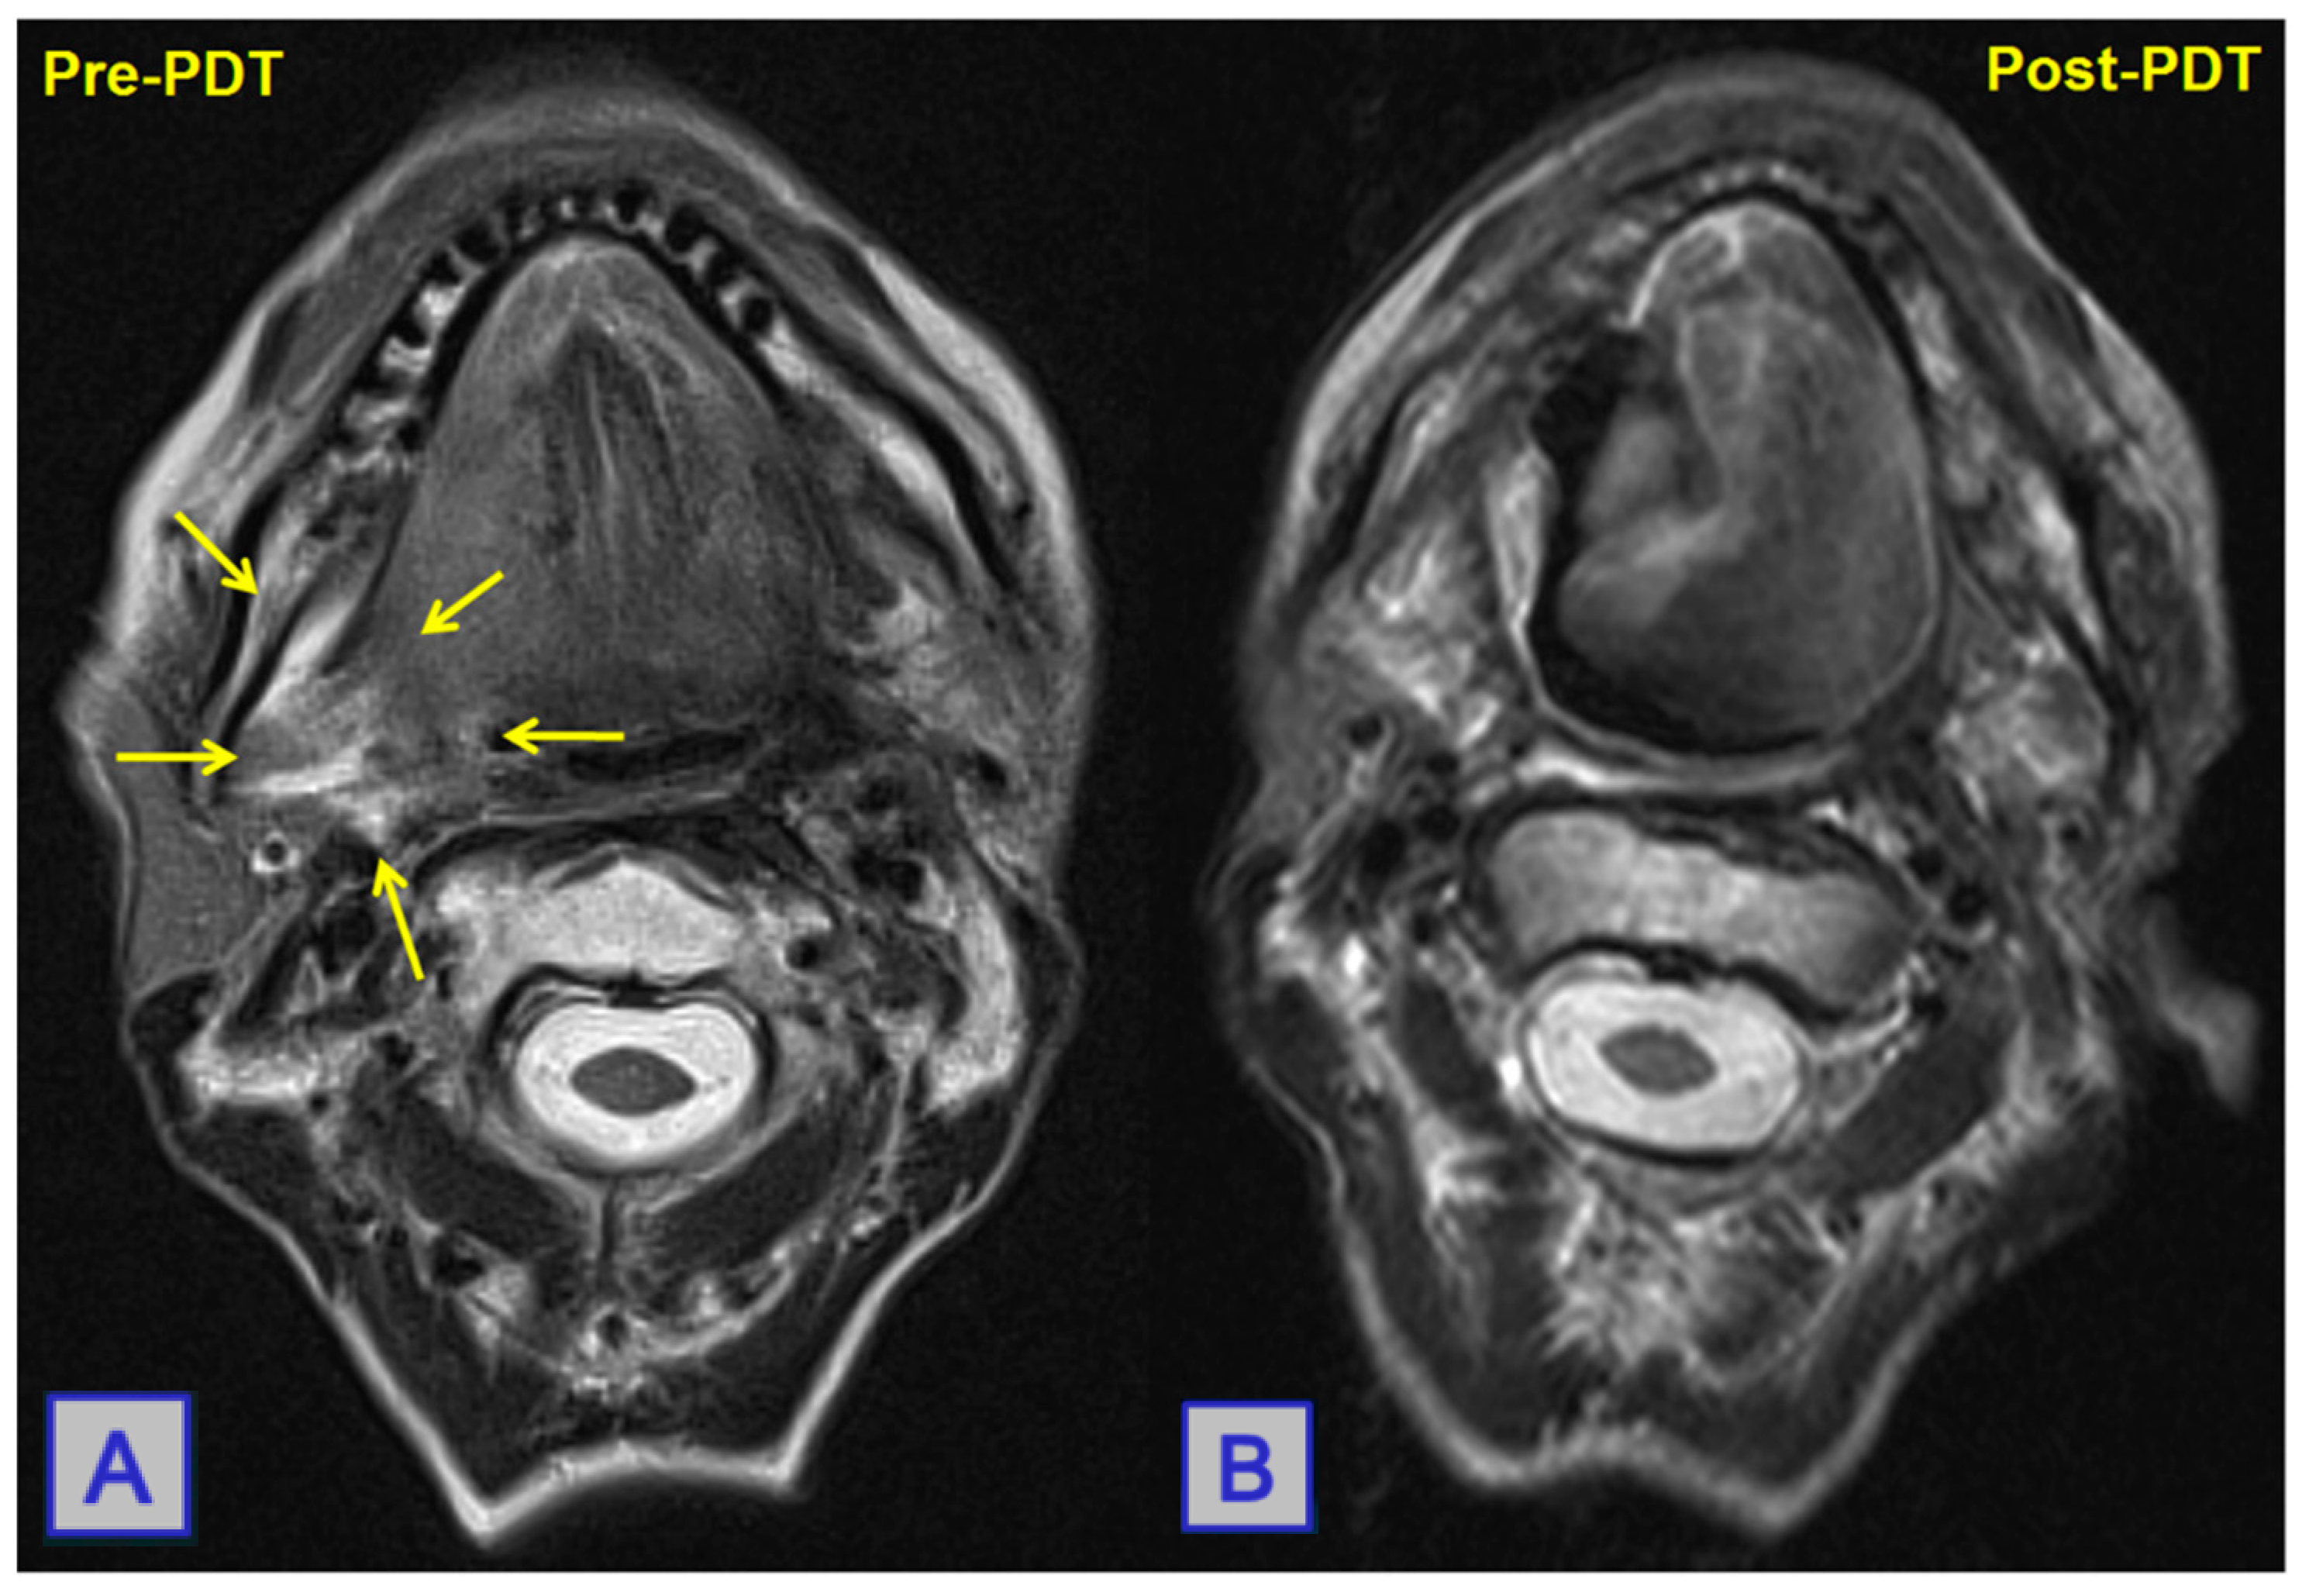

- Jerjes, W.; Upile, T.; Hamdoon, Z.; Abbas, S.; Akram, S.; Mosse, C.A.; Morley, S.; Hopper, C. Photodynamic therapy: The minimally invasive surgical intervention for advanced and/or recurrent tongue base carcinoma. Lasers Surg. Med. 2011, 43, 283–292. [Google Scholar] [CrossRef]